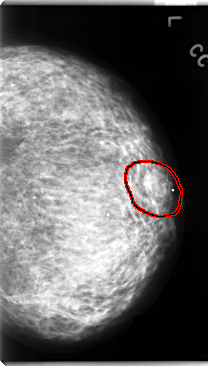

C_0130_1.LEFT_MLO

LEFT_MLO LINES 4704 PIXELS_PER_LINE 2824 BITS_PER_PIXEL 12 RESOLUTION 50 OVERLAY

FILE: C_0130_1.LEFT_MLO.OVERLAY

TOTAL_ABNORMALITIES 1

ABNORMALITY 1

LESION_TYPE MASS SHAPE IRREGULAR MARGINS ILL_DEFINED

ASSESSMENT 4

SUBTLETY 1

PATHOLOGY MALIGNANT

TOTAL_OUTLINES 1

BOUNDARY